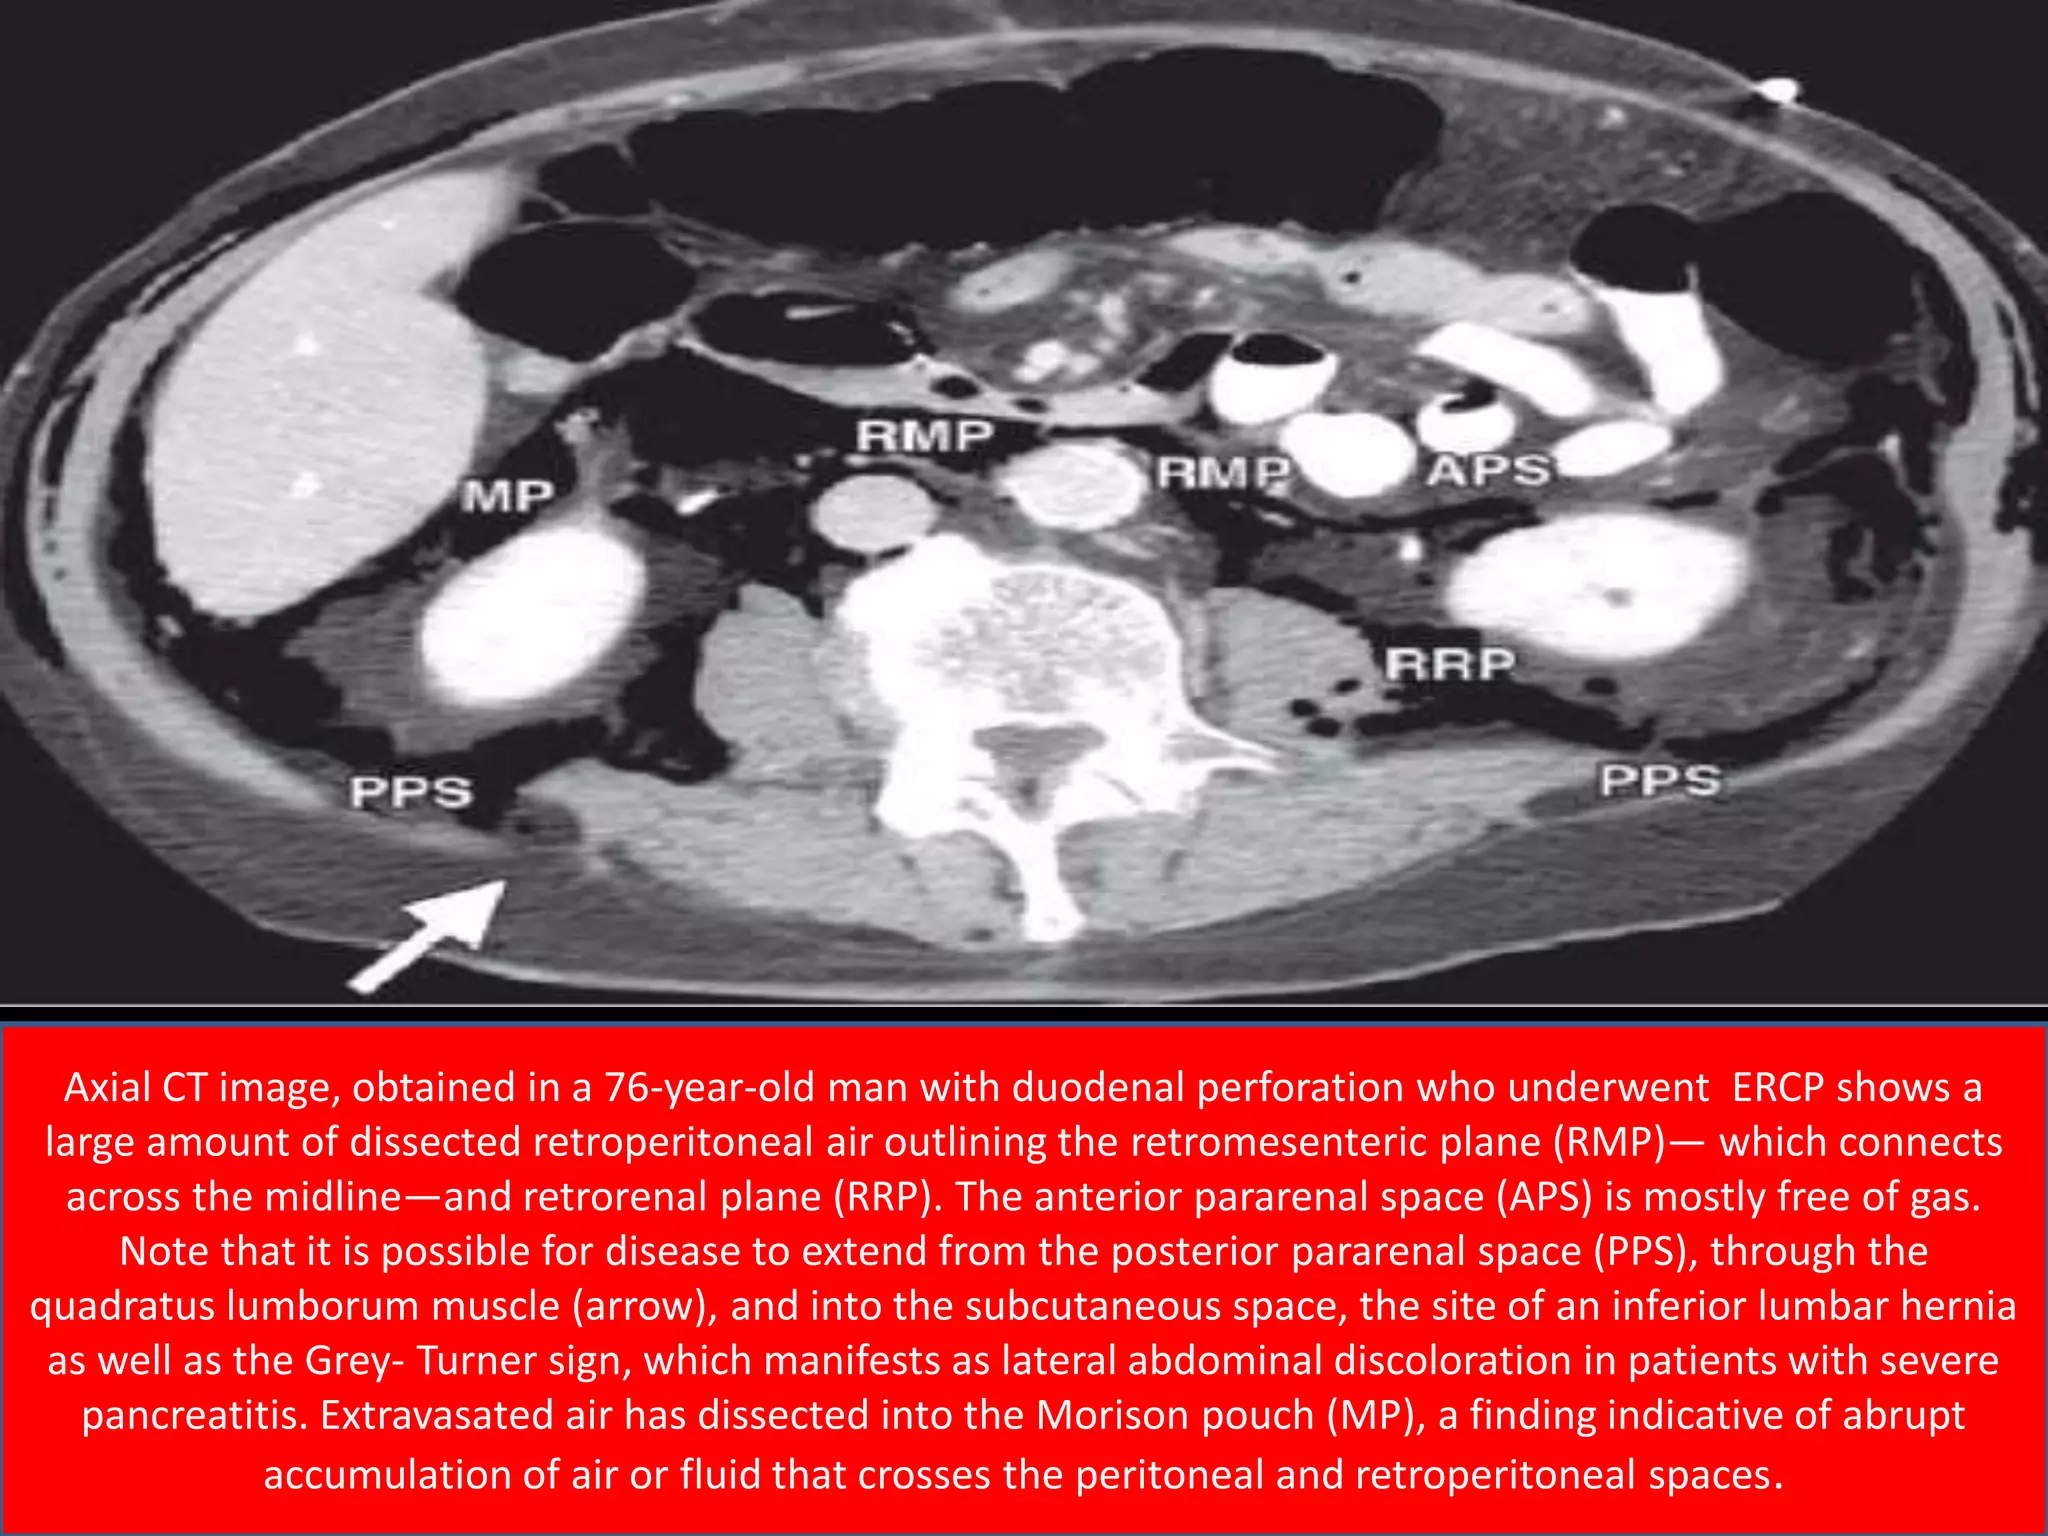

Axial CT image, obtained in a 76-year-old man with duodenal perforation who underwent ERCP shows a

large amount of dissected retroperitoneal air outlining the retromesenteric plane (RMP)— which connects

across the midline—and retrorenal plane (RRP). The anterior pararenal space (APS) is mostly free of gas.

Note that it is possible for disease to extend from the posterior pararenal space (PPS), through the

quadratus lumborum muscle (arrow), and into the subcutaneous space, the site of an inferior lumbar hernia

as well as the Grey- Turner sign, which manifests as lateral abdominal discoloration in patients with severe

pancreatitis. Extravasated air has dissected into the Morison pouch (MP), a finding indicative of abrupt

accumulation of air or fluid that crosses the peritoneal and retroperitoneal spaces.